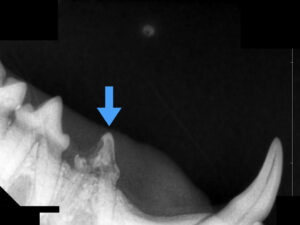

下の写真を御覧ください。

この猫ちゃんは小さい頃の交通事故で顎の骨が歪んでしまい、歯並びがずれてしまいました。

青矢印で示した下の歯が長い年月をかけて上顎の口蓋にあたり、潰瘍化した後に穴が空いてしまったのだと推測されます。

この穴は鼻腔に達していて、食事や飲水のたびにくしゃみや鼻水などの症状に悩まされているとのことでした。